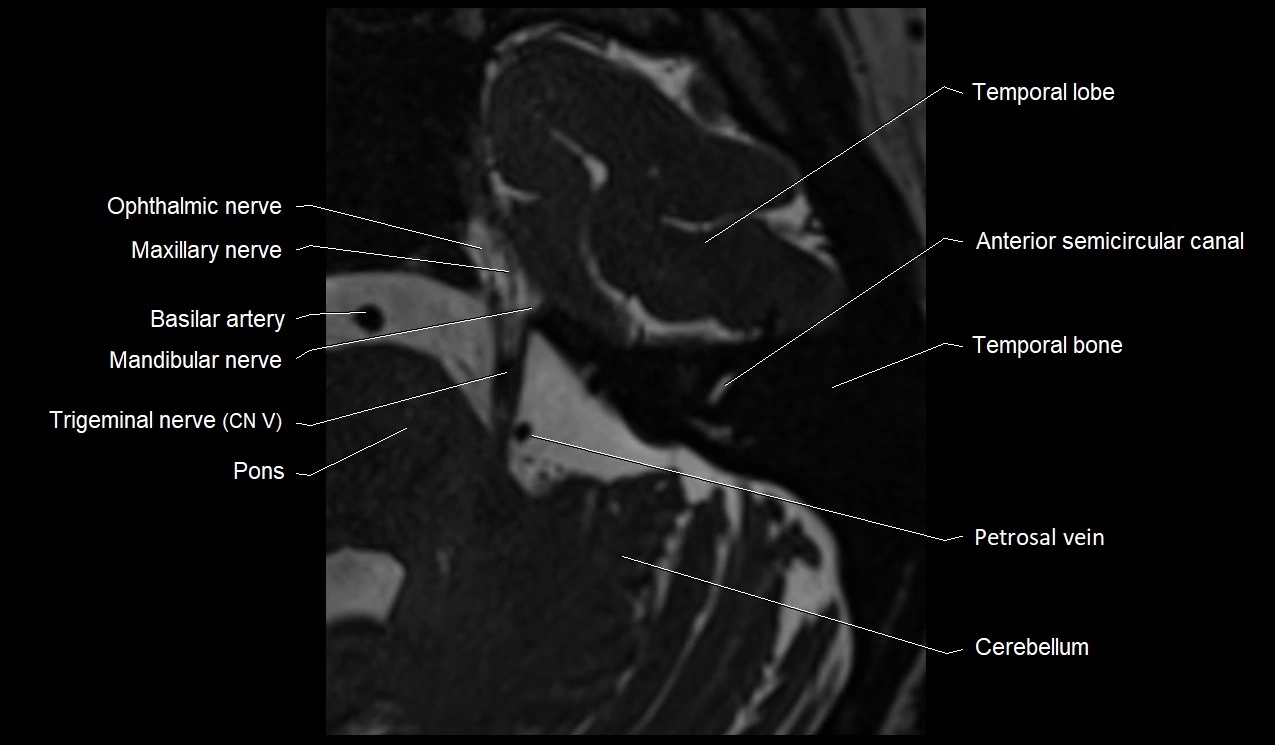

• Best visualized on high-resolution T2-weighted 3D MRI sequences (e.g., FIESTA or CISS)

• Seen as a hypointense (dark) line running from the brainstem at the pontomedullary junction, traversing the prepontine cistern, and entering Dorello’s canal under the petrosphenoidal ligament, then into the cavernous sinus, and finally the orbit